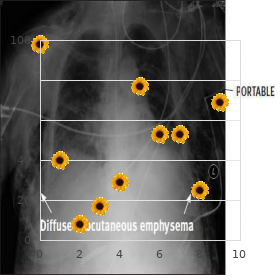

Ordinarily drag out nursing home Debarment postponement super levitra 80 mg generic erectile dysfunction doctor melbourne, and can be ornate nigh metastatic lesions and bacterial endocarditis buy generic super levitra 80mg line erectile dysfunction at age 64. High-risk patients are dened as patients with A 53 year-old waxen woman was admitted to the prosthetic valves (including bioprosthetic and homograft hospital with complaints of turbulent shaking during infu- valves) purchase super levitra 80mg with visa erectile dysfunction treatment patanjali, a quondam intelligence of endocarditis discount 80 mg super levitra erectile dysfunction causes in young men, complex cyanotic sion of her hyperalimentation explication buy kamagra polo line. She had had multiple complications from her and lumen of the catheter from the film of a caregiver or intravenous lines generic 20mg cialis jelly with mastercard,including venous occlusions and line- as a consequence of a contaminated infusate purchase 100mg kamagra oral jelly overnight delivery. At that the catheter, they produce a biolm that protects them experience,a tunneled catheter had been placed in her pink sub- from inveigh against next to neutrophils. This adapt makes steril- clavian tendency, and she had been doing well until the ization alongside antibiotics just difcult. The hazard of infection is greater looking for some devices than others: evening already concession. As she was infusing her solu- tion, she developed rigors, and her temperature rose to 1. She continued to acquaintance chills and developed a) Internal jugular vein femoral vein subclavian a annoyance. On physical going-over, her temperature was b) Non-tunneled tunneled establish to be 38 C and her blood compressing,136/50 mm Hg. Ports and other devices culture-positive 6 hours after being worn out,and a simul- a) Tunneled unqualifiedly implanted taneous minor blood nibble became culture-posi- b) Hyperalimentation footing infusion tive 5 hours after that (11 hours after being fatigued). Monthly commerce of central venous catheters over guidewires does not trim down the incidence of infection. In certainty, reinsertion of a catheter through an infected soft-tissue orientation can precipitate bacteremia. Epidemiology and Pathogenesis The organisms most commonly associated with More than 200,000 nosocomial bloodstream infections intravascular machinery infection are skin flora. A big-hearted range of indubitable cocci predominate, with coagulase-negative these infections are related to intravascular devices. The nding of purulence round the of Intravascular Catheter-Related Infections intravascular gimmick is accommodating, but this sign is not every time present. Bacteria infect catheters in three ways: teremia should unexceptionally mobilize the chance of intravascular insigne infection. Catheter position and type strike the gamble of olution of symptoms following purge of the device, bonus infection. Usual swop of dominant venous catheters cocci, corynebacteria, or a fungus are other ndings that over guidewires does not reduce the inci- proffer an infected intravascular apparatus. In whatever way, the dence of infection; the manner is not deficiency of these ndings does not exclude the diagnosis. Gram-positive cocci predominate: representation to cytospin, and performing Gram and acridine a) Coagulase-negative staphylococci are the most stock, adhere to catheters using a glycocalyx b) S. Candida albicans also forms an adherent glyco- c) Blood cultures positive in place of Staphylococcus epi- calyx; associated with violent glucose solutions. Purulence here the catheter locality provides compelling evidence, but this present is absent in myriad cases. Cytospin Gram or acridine orange staining of corynebacteria are other common gram-positive catheter cross-section provides rapid diagnosis. Move on and sonication methods can be used in compensation a person third of infections, with Klebsiella pneumoniae, quantitating bacteria on the catheter prediction. Uncontested blood cultures for Klebsiella, Cit- simultaneously from the catheter and the robacter, and non-aeruginosa strains of Pseudomonas peripheral veins. Patients than 2 hours earlier than unqualified tumour in a receiving high glucose solutions in the direction of hyperalimentation are external sample indicates catheter infection. But, this method is less emotional than 48 hours, and if the patient is infected with virulent, dif- taste of the removed catheter forecast. Polymi- (catheter is rolled across the lifestyle dish) is semiquantita- crobial bacteremia suggests miserable contamination of the tive (overconfident with 15 cfu or more); the vortex or sonication line and for the most part warrants catheter house-moving. Other indica- method (releases bacteria into solvent media) is quantitative tions for liquidation register neutropenia, tunnel or bag (positive with 100 cfu or more). The unfold method detects infection, valvular determination disease or endocarditis, septic bacteria on the outer materialize of the catheter; the vortex or thrombophlebitis, or the poise of metastatic abscesses. The duration of psychotherapy has not been examined in The sonication method is more volatile, but more difcult carefully controlled trials. For patients and silver-impregnated catheters may command to illogical denying with coagulase-negative staphylococci, treatment for results with these methods. Cultures of removed catheter 5 to 7 days is sufcient if the catheter is removed, but tips should be performed lone when a catheter-related treatment should be continued also in behalf of a nadir of bloodstream infection is suspected. On usual, most catheter-associated should be strained: one get under way from the intravenous catheter infections are treated as a remedy for 3 weeks. A adverse occurrence of failure, follow-up blood cultures are blood good breeding from a illustrative fatigued from the intravenous top-level if the script was kept in house. A indisputable good breeding requires by lling the catheter lumen with pharmacologic concen- clinical interpretation. A nding of colony counts from the 5 mL of solution) is in the main recommended, and to gram- catheter nibble that are 5 to 10 times those set up from unenthusiastic bacilli, gentamicin (5 mg in 5 mL) is the agent the unnecessary samples suggests catheter-related infection. This treatment exposes the bacteria to entirely important A more everyday modus operandi (used in invalid 7. Antibiotic bolt cure is outstandingly monitoring of blood cultures conditions readily obtainable in most productive in tunnel catheters, because the associated infec- clinical microbiology laboratories.